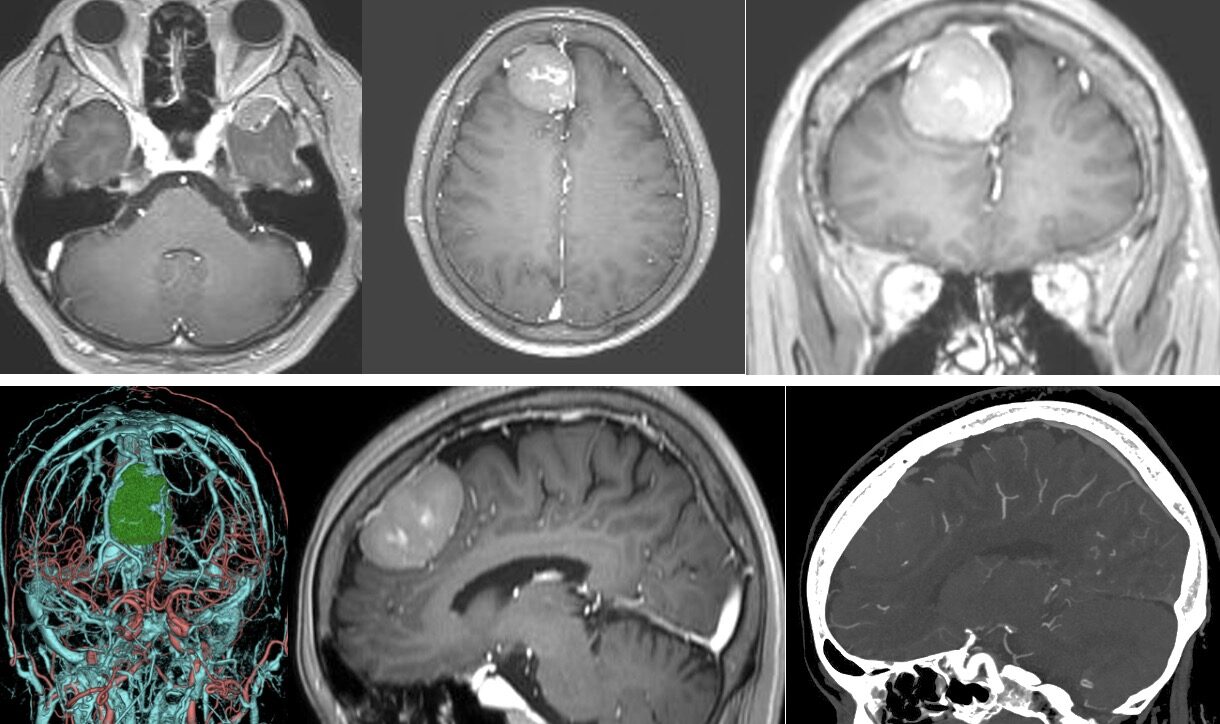

2023/6月 71F 右傍矢状髄膜腫を摘出しました

進行する歩行障害のために手術を決断されました。術前の血管撮影で静脈洞が流れていなかったので、SSSの前方部分をFalxの一部を含めて合併切除しSimpson grade 1の完全摘出を達成しました。腫瘍は全摘出され、術後脳浮腫やてんかんなど合併症は全く生じませんでした。術後歩行障害のリハビリを行い、現在元気に外来通院されています。